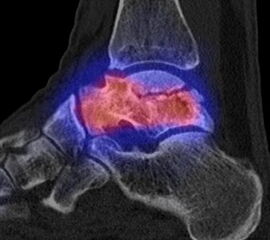

Abbildung 9.1.a bis d: Insuffizienzfraktur bei einer Patientin mit bekannter Osteoporose und chronischen rechtsseitigen Fußschmerzen. Es wurden 3 MRT-Untersuchungen in 9 Monaten durchgeführt (!), welche wechselnde Ödeme in den Fußwurzelknochen zeigten ohne dass eine eindeutige Diagnose formuliert wurde. Die SPECT/CT zeigt den typischen Aspekt einer Insuffizienzfraktur im vorderen Abschnitt des Calcaeus mit hypermetabolen linearen intraspongiösen Verdichtungen; im MRT (5 Wochen vor der SPECT/CT angefertigt) "nur" ödematöse Knochenmarkveränderungen.